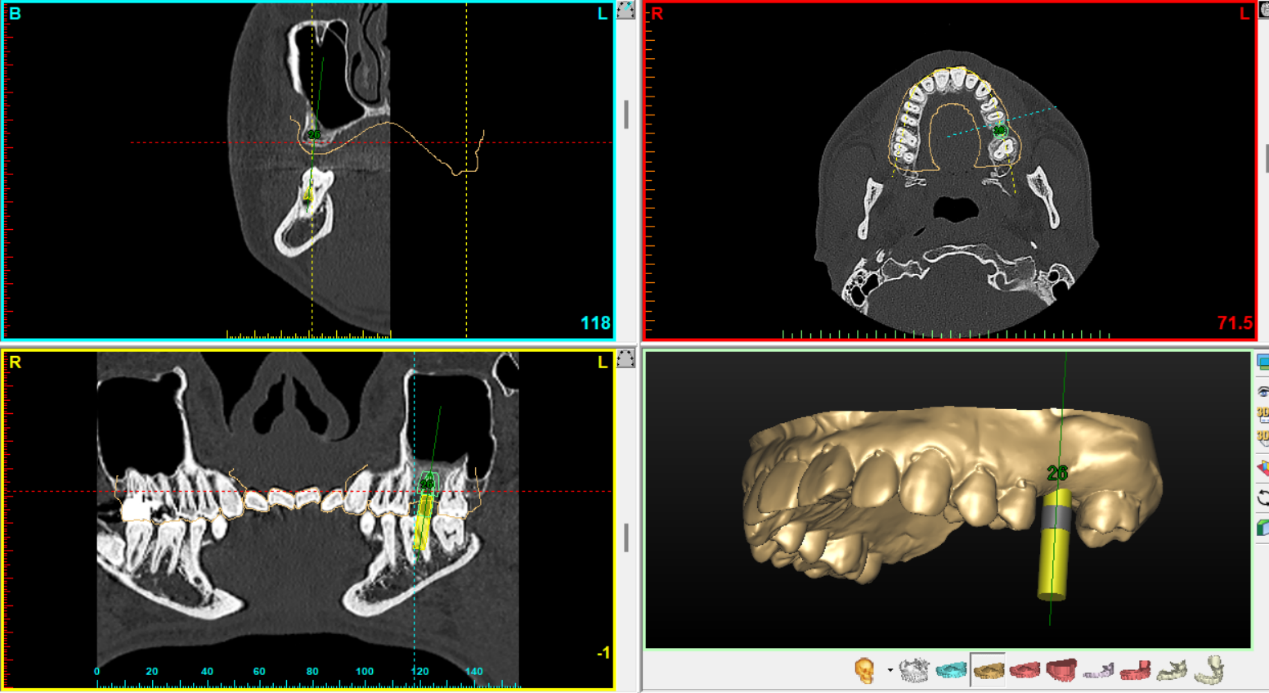

3Dコンピューターシュミレーションシステム

3Dコンピューターシュミレーションシステムを用いて治療計画を行い、サージカルガイドを使用することで、より確実な位置への埋入、合併症の回避に努めています。